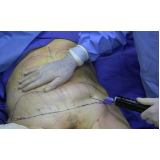

Lipoaspiração a Laser

Você merece a qualidade e comprometimento entregues pela equipe deste consultório médico e se neste momento está à procura de uma equipe que realize lipoaspiração a laser saiba que a FF Cirurgia Plástica disponibiliza de imediato este serviço para você!